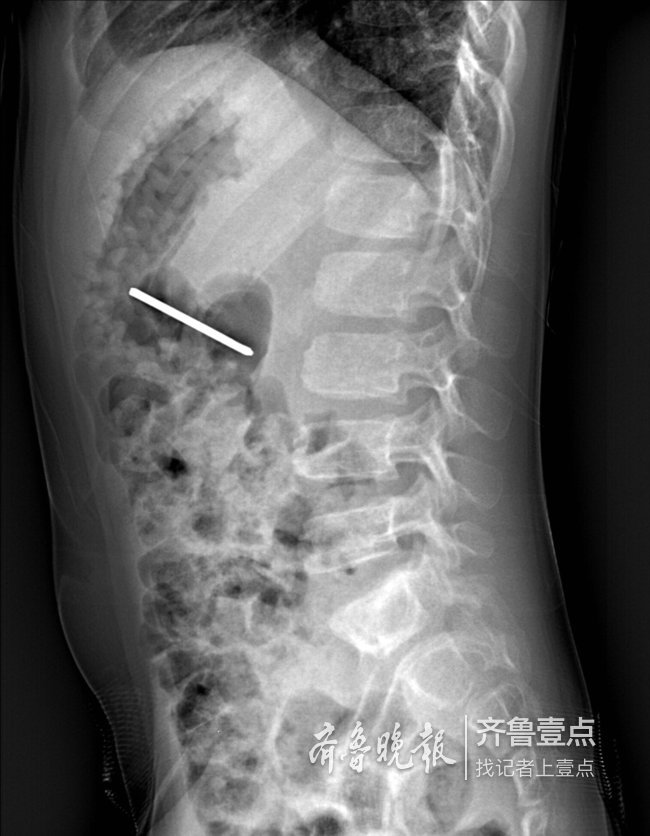

泰安一6岁男孩误吞5cm钢针 胃镜巧取免开腹之痛